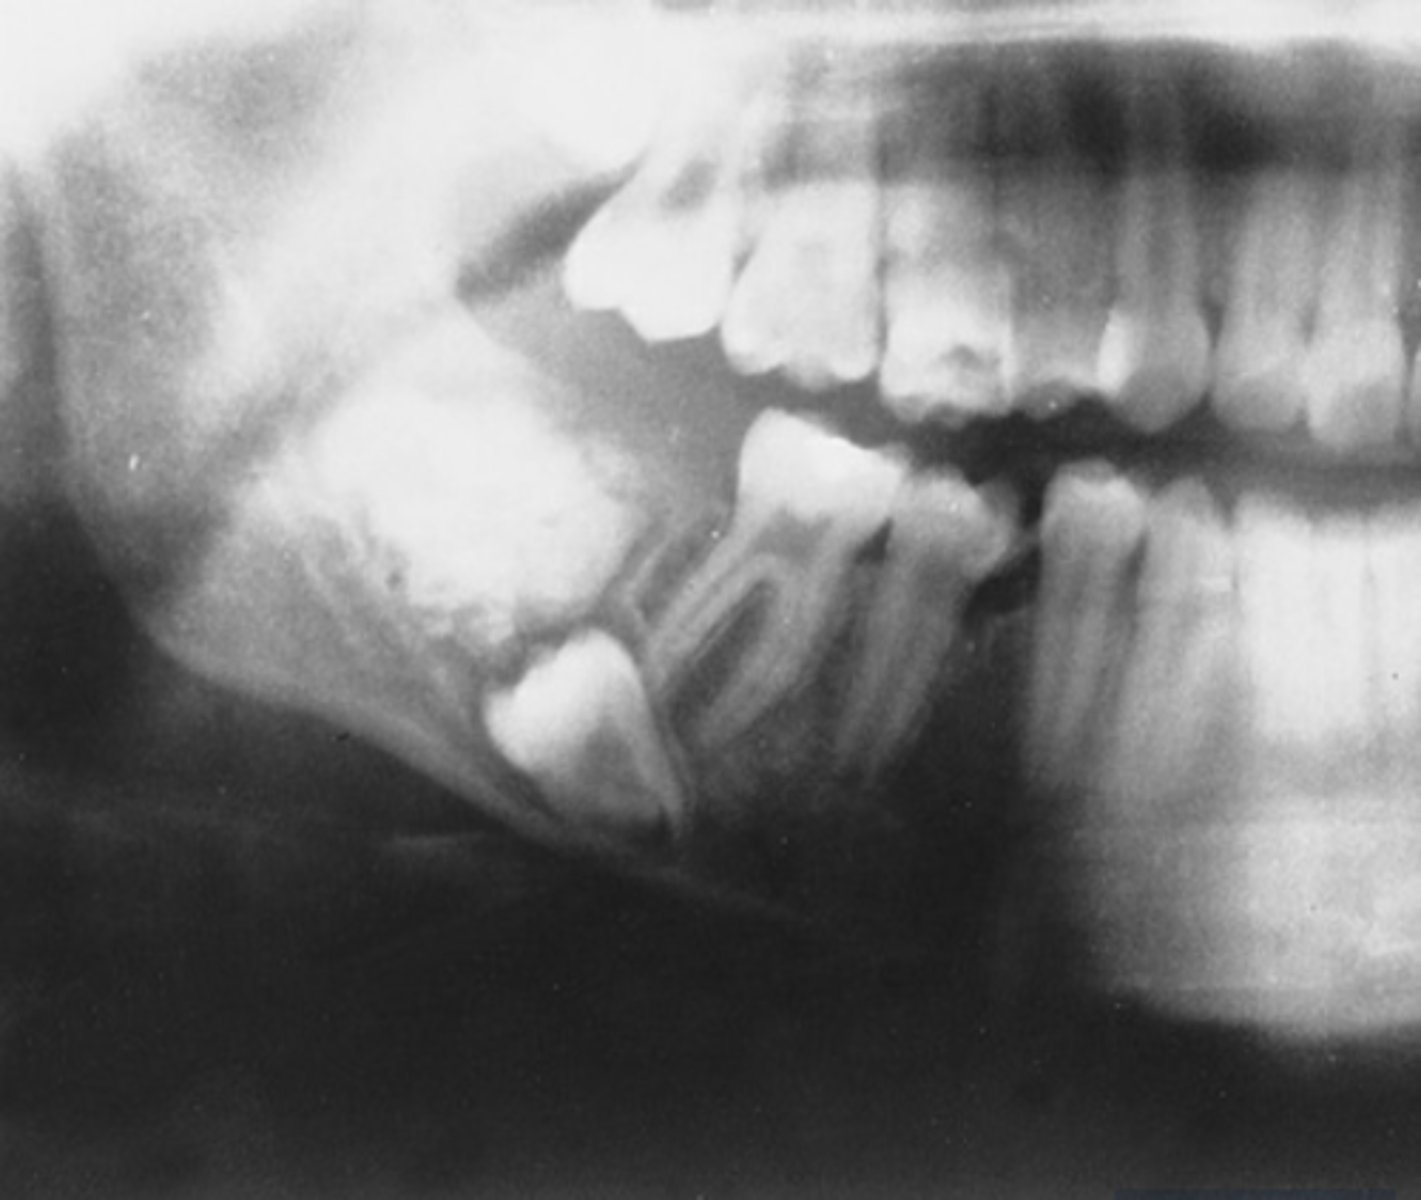

What are the radiographic features of ameloblastomas?

⢠unilocular radiolucency (early lesions)

⢠multilocular radiolucency (honeycomb/soap bubble) (large lesions)

⢠cortical thinning/bone expansion

⢠resorption of adjacent tooth roots + tooth displacement